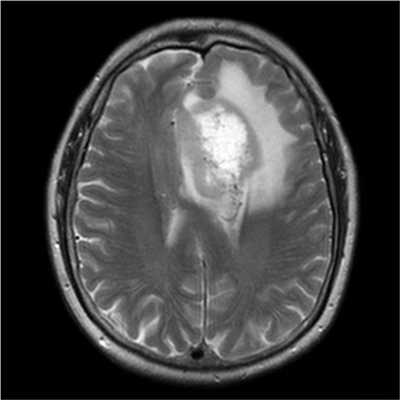

Злокачественные опухоли характеризуются инвазивностью, то есть врастанием в здоровые ткани, поэтому контуры таких образований нечеткие и неровные, а потому достоверно определять границы таких опухолей довольно сложно. Кроме того, структура злокачественной опухоли часто бывает неоднородна за счет распада (некроза), кровоизлияния и коллоидной дегенерации. Вокруг злокачественной опухоли, как правило, выявляется выраженный перифокальный отек, который может приводить к смещению срединных структур головного мозга и появлению аксиальной дислокации. Также могут быть выявлены признаки метастазирования.

Как выглядят метастазы на МРТ

На снимках метастазы выглядят, как очаговые неоднородные образования, единичные или множественные, с тенденцией к слиянию, может присутствовать зона некротизации. Пораженный лимфатический узел чаще округлой формы, увеличен в размерах. Для лучшей визуализации используют контрастное вещество на основе солей гадолиния.